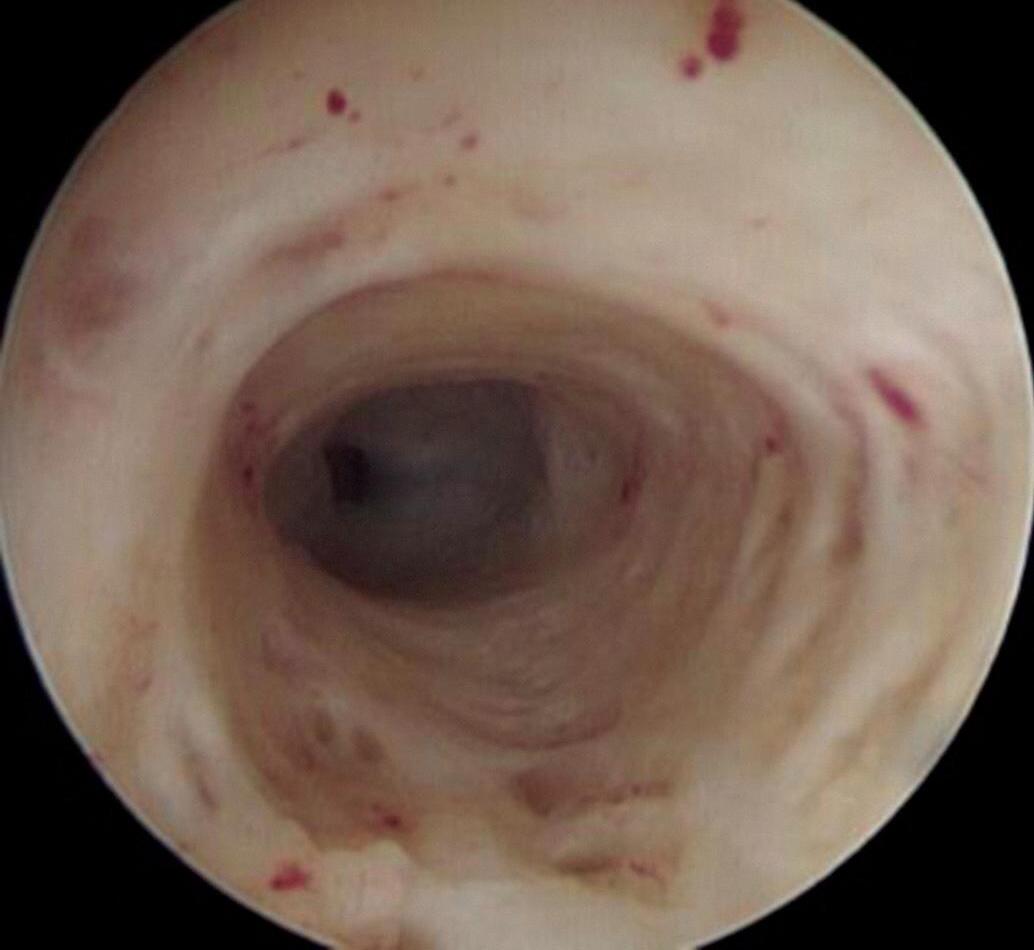

A introdução do histeroscópio por vaginoscopia permite boa avaliação do canal vaginal e sua mucosa. A ectocérvice é a porção do colo que se estende do orifício cervical externo (OCE) aos fórnices da vagina e é revestida por epitélio estratificado escamoso, ou parcialmente por epitélio colunar, na presença de ectopia. O aspecto do OCE costuma variar dependendo da paridade e da condição hormonal da paciente (Figs. 1-1 a 1-3).

Apoiar a ponta da ótica no OCE do colo permite que o meio líquido distenda o canal endocervical; a época ideal para a avaliação do canal é a fase pré-ovulatória do ciclo, quando o muco está menos viscoso (mais fluido), livre de partículas e se desprende facilmente com o líquido. Na segunda fase o muco é mais viscoso e turvo, adere com maior firmeza à ótica, dificultando a visualização. O canal possui um formato fusiforme, mede geralmente de 2,5 a 3 cm de comprimento e diâmetro que pode variar de 3 a 10 mm. Costuma ser dividido em três partes, devido às suas diferentes características. O aspecto do canal varia de acordo com a condição hormonal da paciente.

A superfície do canal, sob estímulo estrogênico, costuma apresentar-se de coloração rosada e recoberta por tecido glandular, com abundante muco no seu interior. Estruturas fibrosas da porção mais profunda da parede não costumam ser visualizadas.

Primeiro Terço do Canal ou Terço Proximal/Inferior

Observam-se as papilas, que apresentam aspecto semelhante a minúsculos grãos de uva agrupados entre si. Especialmente no terço inicial do canal podemos observar as pregas da mucosa, que são pequenas elevações longitudinais, separadas entre si por depressões profundas, denominadas de criptas. As criptas (depressões na superfície da mucosa) podem ser observadas na profundidade da mucosa, quando se separam as pregas (Fig. 1-4).

Fig. 1-4. (a-c) Imagem das papilas e pregas do terço proximal do canal e do muco claro. (Fonte: arquivo pessoal do autor.)